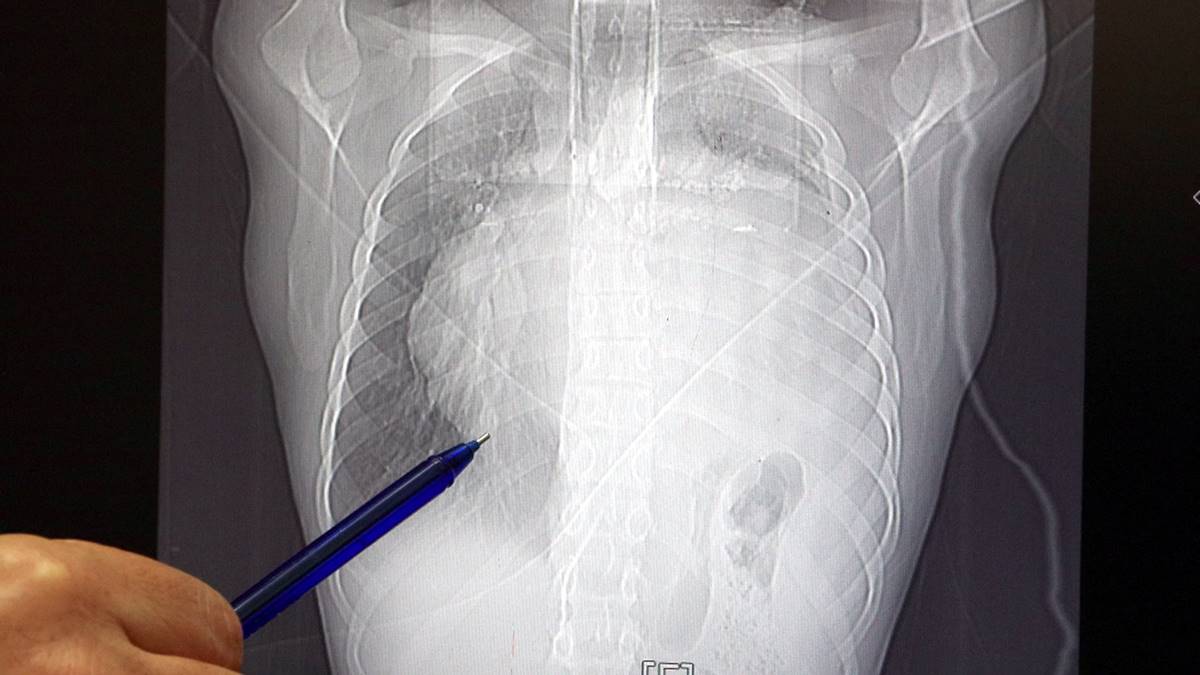

İstanbul'da yaşayan 21 yaşındaki Burak Aktaş, 2023 Temmuz ayında işe girmek üzere sağlık raporu almak için hastaneye gitti. Her şey yolundaydı ve raporunu alarak iş başı yaptı. Bir ay geçmeden nefes darlığı, halsizlik, öksürük gibi şikayetlerle başka bir hastaneye gittiğinde ise ilk şoku yaşadı. Sol göğüs boşluğunda portakal büyüklüğünde bir kitle tespit edilmişti.

Yapılan biyopside tümörün akciğer kaynaklı olmadığı, henüz cenin aşamasında eşey hücrelerinin farklılaşmasıyla gelişen 'immatür teratom' teşhisi kondu. Kitleyi küçültmek için kemoterapi uygulansa da tam tersine tümör 2 ay içinde neredeyse 10 katına çıktı ve büyük bir karpuz boyutuna ulaştı.

Sol akciğerinin yüzde seksenini kağıt gibi ezen, kalbini göğüs duvarında 12 santim sağa kaydıran ve hem kalbe hem beyne giden ana damarlara baskı yapan 6.5 kilo ağırlığındaki dev tümör, Koşuyolu Yüksek İhtisas Eğitim ve Araştırma Hastanesi Göğüs ve Kalp Damar Cerrahisi ekiplerinin birlikte girdiği operasyonla başarılı şekilde çıkarıldı.

"Bundan 2,5-3 ay öncesine kadar hiçbir problemi olmayan, hayatını normal devam ettiren bir delikanlı Burak. Göğüs ağrısı öksürük ve nefes darlığı şikayetiyle sağlık kuruluşuna başvuruyor. Orada yapılan tetkiklerinde sol göğüs boşluğunda akciğerinden kaynaklanmayan portakal büyüklüğünde bir kitle tespit ediliyor ve immatür teratom tanısı konuyor.

2 ay arayla yapılan tetkiklerinde ve arada cerrahi öncesi küçültme amaçlı kemoterapi almasına rağmen, portakal büyüklüğündeki tümör, irice bir karpuz büyüklüğüne, yaklaşık 6 kilo 300 grama kadar ulaşıyor. Göğüs boşluğunda kemik kafesi içinde olduğu için, itebileceği iki organ var; biri kalp, diğeri de akciğerler.

Soldan sağa doğru büyüdüğü için kalbi tamamen göğüs boşluğunun sağ tarafına itmiş ve kalbe giren ve kalpten çıkan bütün büyük damarları da yer değiştirmenin etkisiyle bükülmüş durumdaydı. Bu nedenle vücuduna yeterince kan gitmiyordu. Ağustos ayının başında portakal büyüklüğündeyken kitle Eylül sonuna irice bir kavun, Ekim ayına geldiğimizde ise bir karpuz büyüklüğüne ulaştığı için, kitlenin büyüme hızı bizi acilen ameliyat yapmaya yöneltti. Yaklaşık 8-10 kat hacimsel olarak artmıştı.